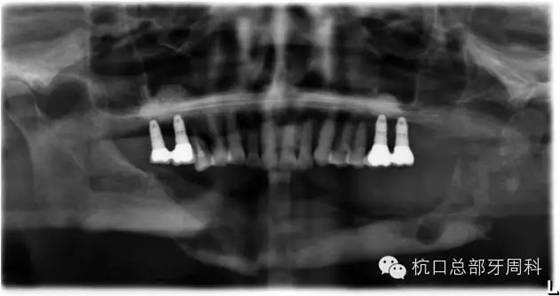

全景片:大范圍火山口樣/彈坑樣骨缺損

初診時全景片2011.7